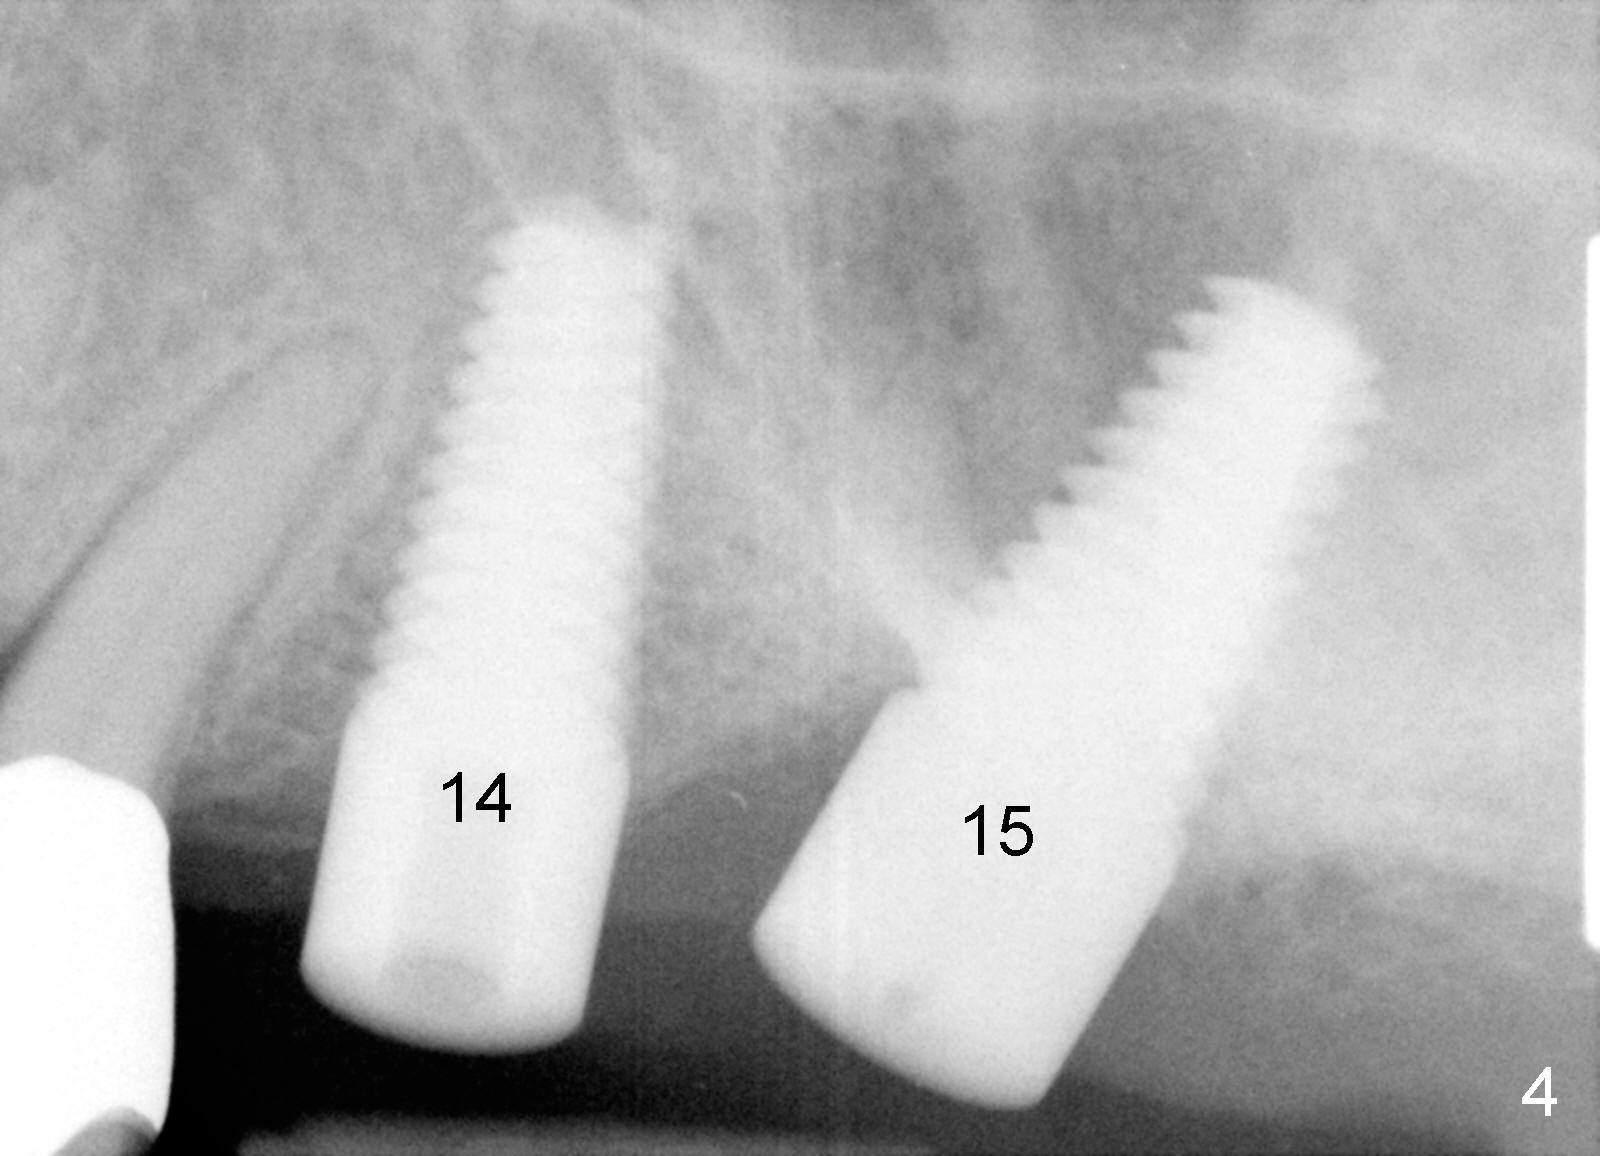

The implant at the site of #14 turned out to be not parallel to the tooth #13 (root) or the implant at the site of #15 (Fig.4), when the retainer (crown) of #13 was used as surgical guide.